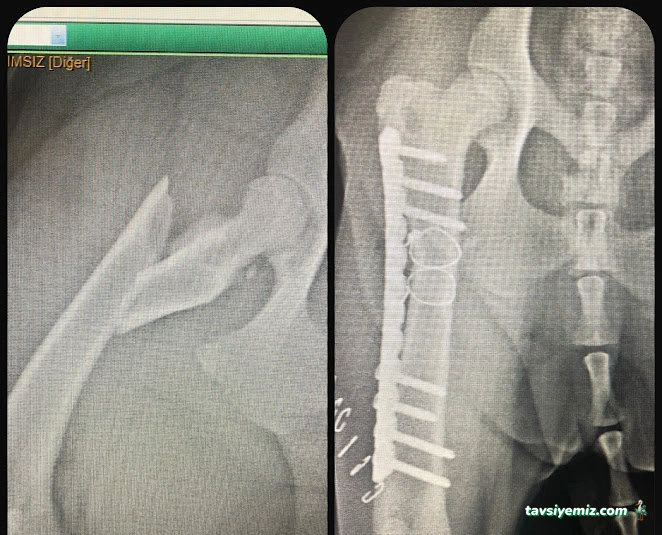

Bornova Doğa Veteriner Polikliniği, rutin aşı uygulamalarından cerrahi müdahalelere, acil müdahalelerden dahili hastalıkların teşhis ve tedavisine kadar geniş bir yelpazede hizmet verir. Küçük ve büyük dostlarınızın sağlığını korumak ve iyileştirmek için en güncel tıbbi yöntemler uygulanmaktadır. Ayrıca laboratuvar testleri, radyolojik görüntüleme ve ultrason gibi ileri teşhis araçları ile hastalıkların erken tanısı mümkün kılınır. Hayvanların yaşam kalitesini artırmayı hedefleyen klinik, aynı zamanda beslenme ve davranış danışmanlığı gibi destek hizmetleri de sunmaktadır.